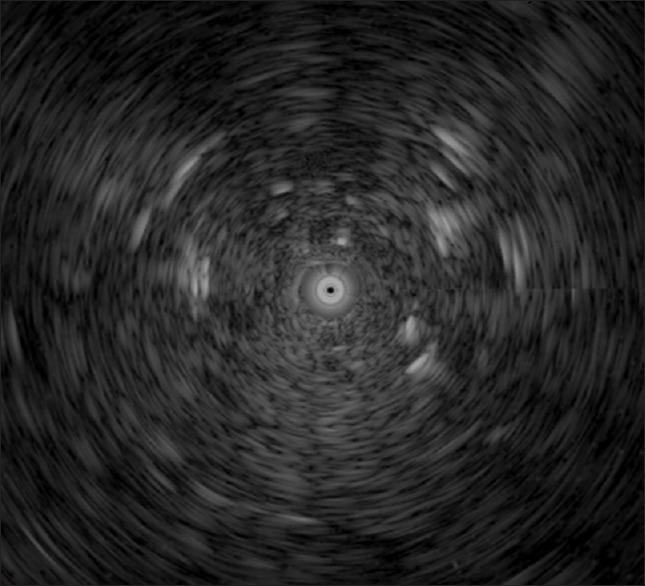

We report a patient with systemic sclerosis who was diagnosed with advanced-stage mucinous adenocarcinoma of the lungs. The clinical presentation, imaging findings, pathological results, and molecular diagnoses are presented. A 64-year-old woman with systemic sclerosis was administered prednisolone and hydroxychloroquine sulfate to control her disease. High-resolution computed tomography (HRCT) revealed an interstitial pattern in both lungs during annual imaging. Connective tissue disease-associated interstitial lung disease (CTD-ILD) was diagnosed using blood tests, pulmonary function tests, and imaging findings. One year later, the patient underwent follow-up chest HRCT, which showed progressive lung disease. The patient underwent endobronchial ultrasound (EBUS)-guided transbronchial lung cryobiopsy and computed tomography-guided biopsy for a pathological diagnosis. The pathology reports of bilateral lungs disclosed mucinous adenocarcinoma. After tumor staging and mutation testing, the patient received chemotherapy with pemetrexed and cisplatin. The bilateral lung lesions subsided after four cycles of first-line chemotherapy. Patients with CTD and lung involvement may be diagnosed with CTD-ILD. Although histopathological results are not mandatory for ILD diagnosis, EBUS-guided transbronchial lung biopsy or lung cryobiopsy should be considered when ILD has atypical or unexplained features.

我们报告了一名系统性硬化症患者,其被诊断为晚期肺黏液腺癌。本文呈现了该患者的临床表现、影像学检查结果、病理结果及分子诊断情况。一名64岁患有系统性硬化症的女性接受泼尼松龙和硫酸羟氯喹治疗以控制病情。年度影像学检查时,高分辨率计算机断层扫描(HRCT)显示双肺呈间质性改变。通过血液检查、肺功能检查及影像学检查结果诊断为结缔组织病相关性间质性肺病(CTD-ILD)。一年后,患者接受胸部HRCT随访,结果显示肺部疾病进展。患者接受了支气管内超声(EBUS)引导下经支气管肺冷冻活检及计算机断层扫描引导下活检以明确病理诊断。双侧肺脏的病理报告显示为黏液腺癌。在进行肿瘤分期及突变检测后,患者接受培美曲塞和顺铂化疗。一线化疗四个周期后,双侧肺部病变消退。患有CTD且有肺部受累的患者可能被诊断为CTD-ILD。虽然ILD诊断并非必须有组织病理学结果,但当ILD具有非典型或无法解释的特征时,应考虑进行EBUS引导下经支气管肺活检或肺冷冻活检。